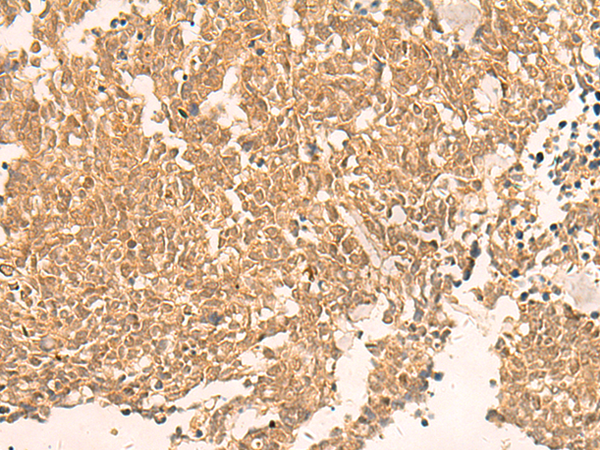

IHC positive control: |

Human gastric cancer and human liver cancer |

IHC Recommend dilution: |

50-200 |